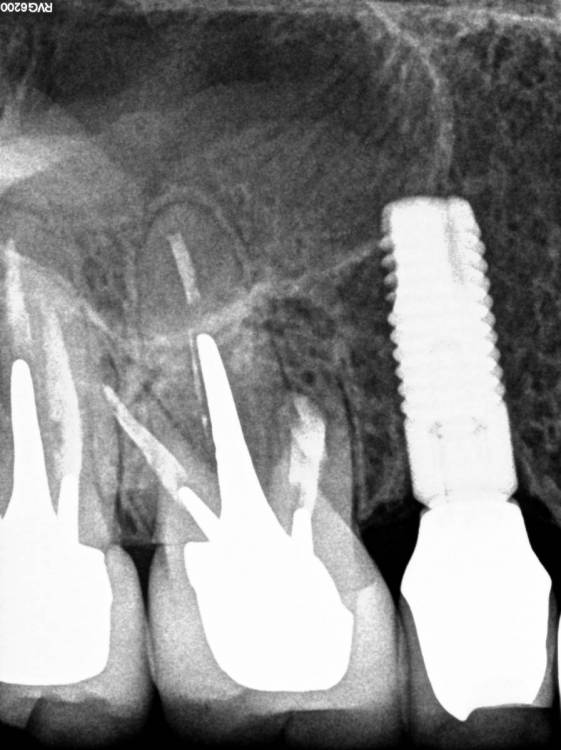

Всем привет!Обострение хронического Pt, ввиду невозможности ортоградной ревизии принято решение об апикальной хирургии.Все манипуляции производятся только под визуальным контролем операционного микроскопа?